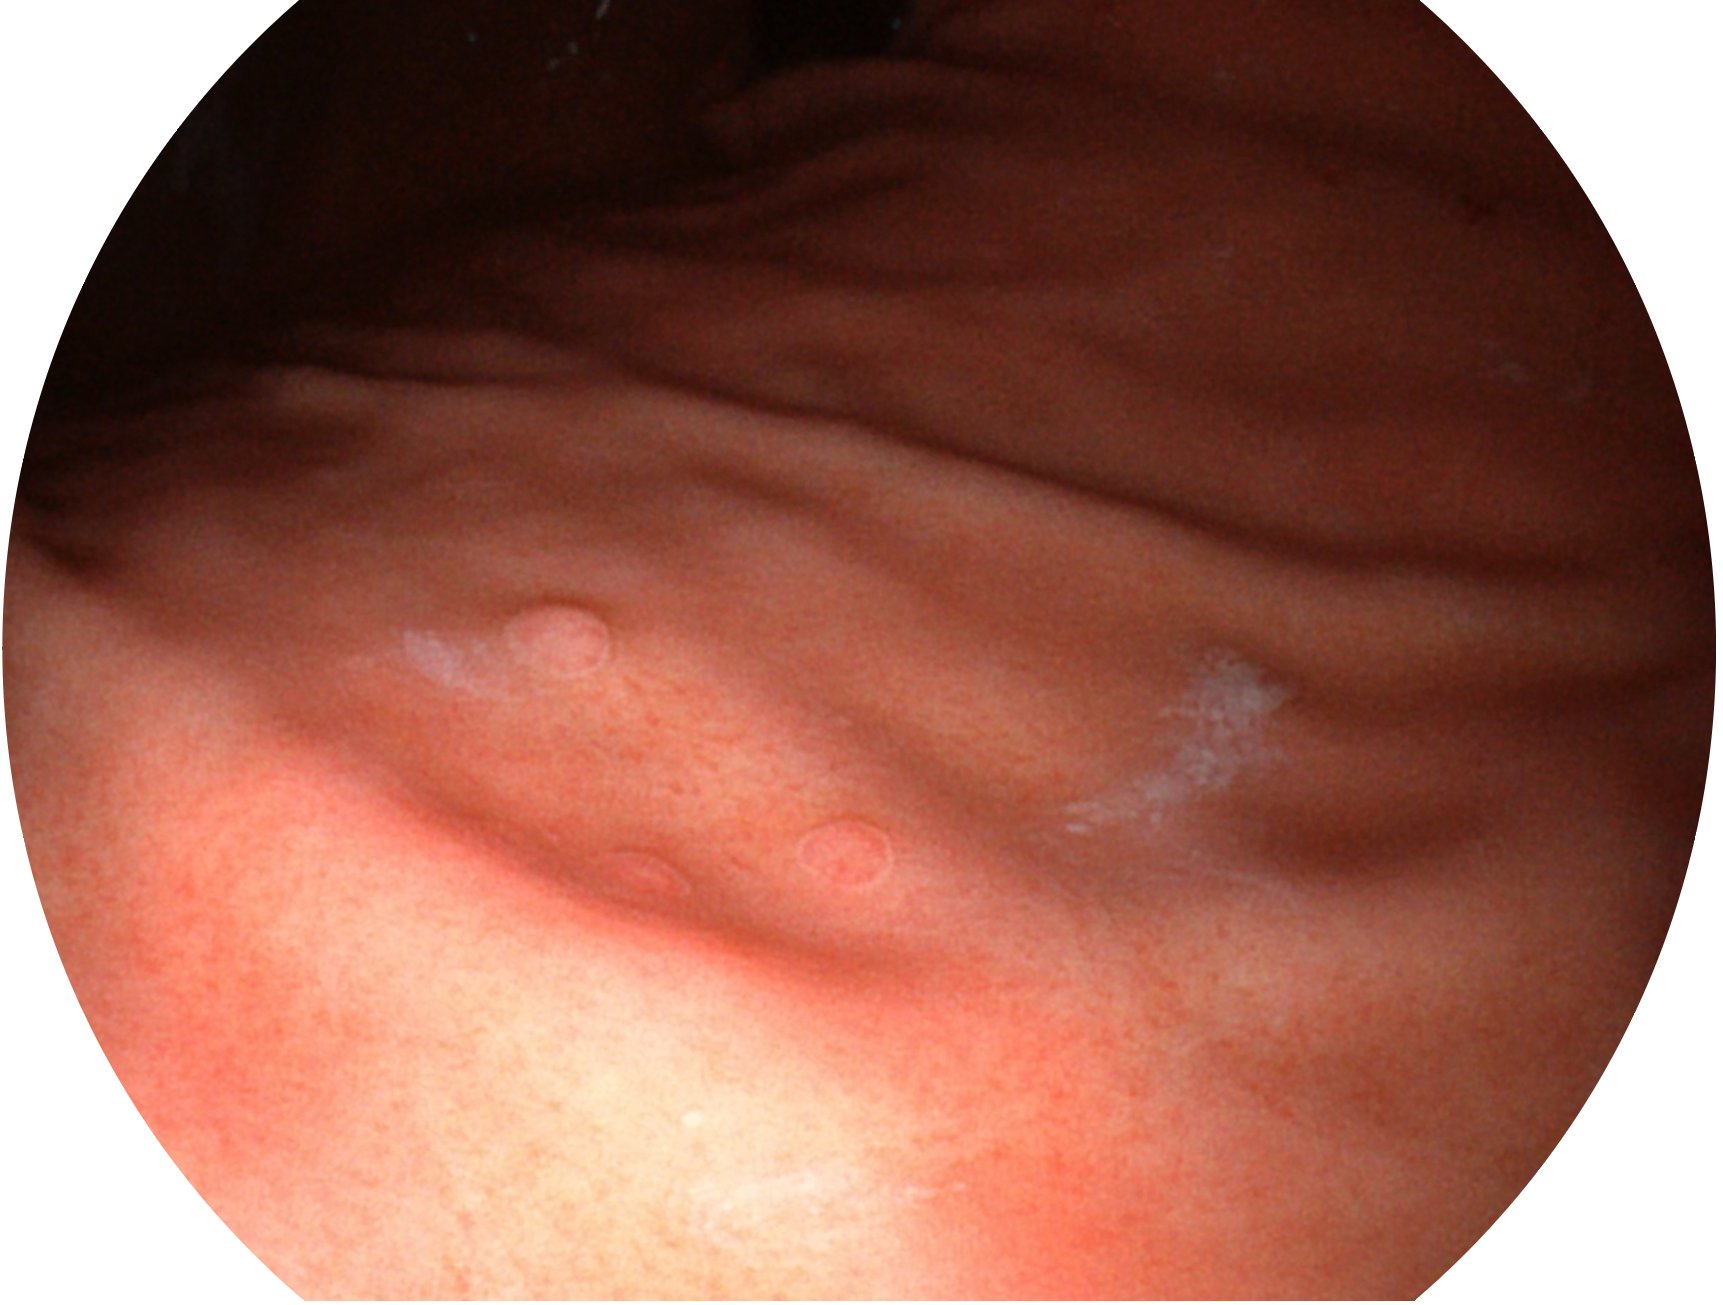

welcome海洋之神新开发的内镜染色技术,主要是基于多波长LED 光源的开发,VLS-55Q 四波长LED 光源是由四个不同颜色的LED光按照相应照明模式所规定的特定发光比例进行合束后形成,合束后形成的照明光的光谱由红光、绿光、蓝光及蓝紫光这四个不同的波段范围构成。具有更高光谱自由度,通过光谱比例的控制,实现了聚谱成像技术,英文全称为“Spectral Focused Imaging, SFI”,缩写为“SFI”和光电复合染色成像技术,英文全称为“Versatile Intelligent Staining Technology, VIST”,缩写为“VIST”。